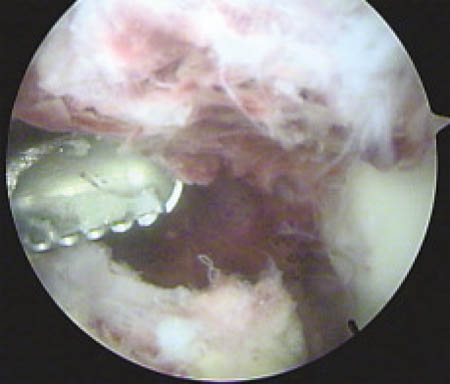

Cada anclaje posee 2 hebras de sutura Fiber-Wire. La primera hebra de sutura que sale del arpón es pasada mediante puntos de Krackow por el extremo proximal del tendón lesionado y a continuación por el remanente tendinoso adherido a la patela, capturando el tendón a lo largo de su línea media. La segunda hebra de cada arpón es pasada en la parte lateral por el primer arpón y la parte medial del tendón por el segundo arpón, para luego realizar el anudado simultáneo de ambos a nivel del polo inferior patelar. (Fig. 5) Luego las lesiones del retináculo medial y lateral son reparadas con Vicryl 1.

Figura 5: Tendón rotuliano reinsertado

Figura 6: Rx Frente Postoperatorio, correcta posición de anclajes óseos.

Figura 7: Rx perfil Postoperatorio, correcta posición de anclajes óseos, correcta altura patelar.

Se realizaron radiografías de control en el postoperatorio inmediato. (Figs. 6, 7)